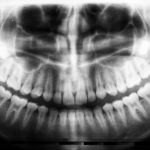

Radiografia digitală cu doză minimă de iradiere

Radiografiile digitale oferă imagini clare și instantanee, cu o expunere la radiații mult redusă față de radiografiile clasice. Ele sunt esențiale pentru diagnostic, pentru verificarea lungimii canalelor și pentru evaluarea rezultatului final.